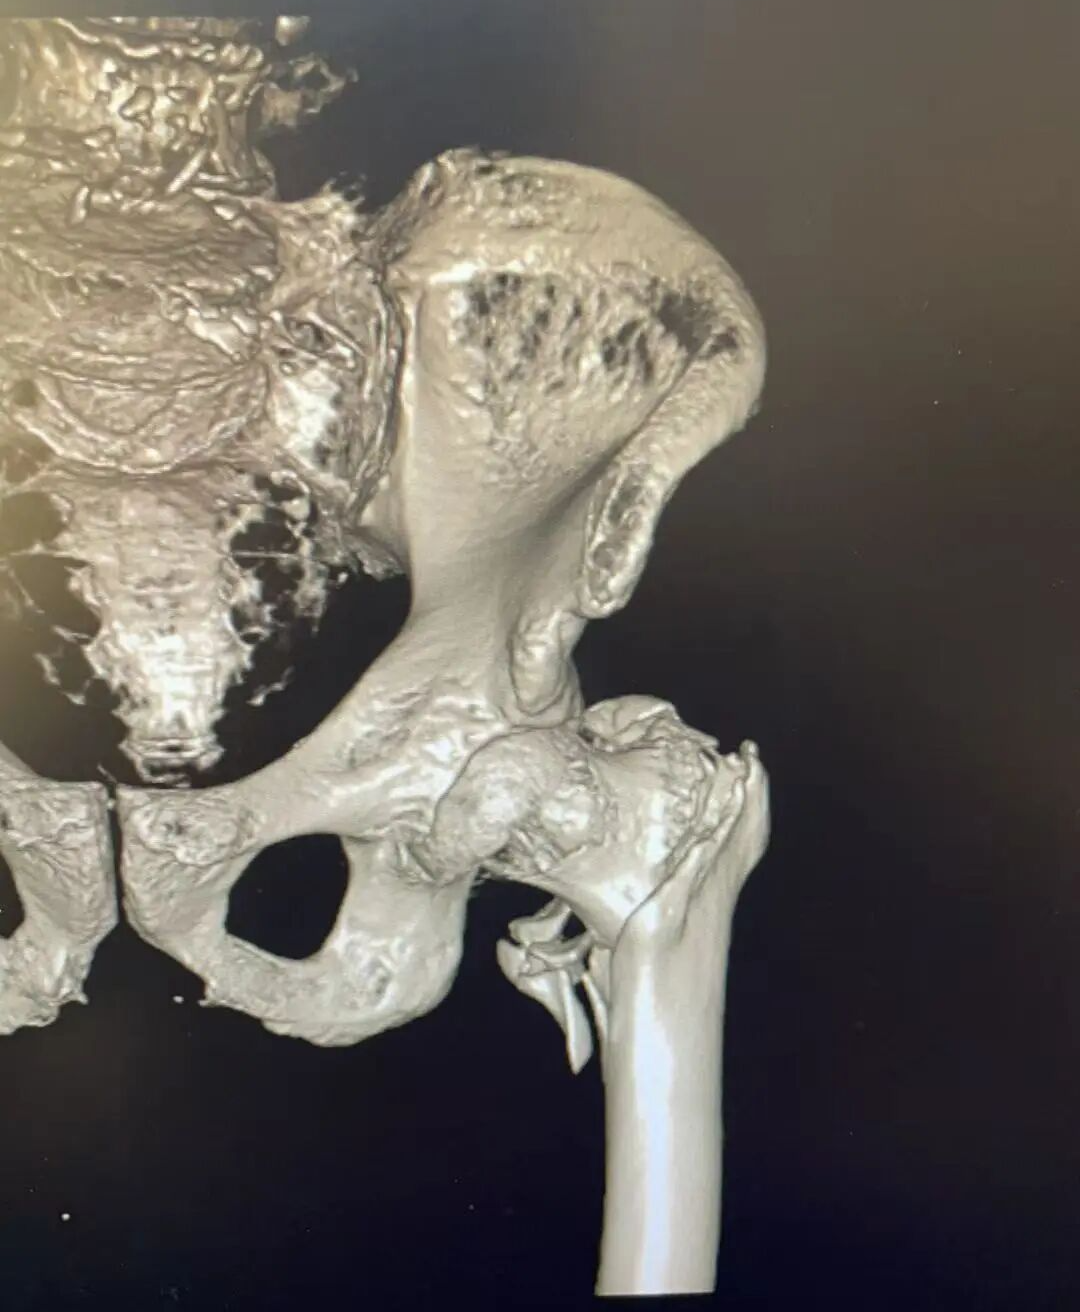

患者术前影像

门诊CT 检查结果明确:右股骨粗隆间粉碎性骨折。骨科团队结合俞大娘的病史、症状及影像检查,综合评估其身体状况后,同样为其制定了 “闭合复位 PFNA 内固定术” 方案。